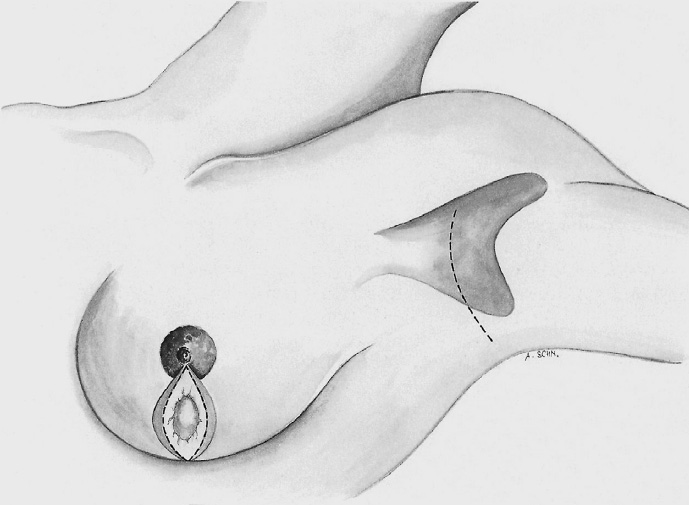

The periareolar skin is de-epithelialized. Here, too, there are various options. A strip of the most superficial skin layer can be excised with dissecting scissors applied flat or with a scalpel. It is important not to leave behind any surface containing squamous epithelium, but on the other hand the dermis and the important vascular layer beneath it must not be injured. The purpose of periareolar de-epithelialization is to recenter the nipple–areola complex and also to tailor excess skin to the new breast shape following extensive tumor resection.

The mobilized breast lobes are rotated into the defect and approximated by interrupted sutures. Complete covering of the defect is desirable.

The skin is closed in two layers with recentering of the nipple–areola complex using interrupted sutures (Vicryl 3–0) according to the preoperative de-epithelialization pattern, which can be corrected at this time.

The skin is closed with an intracutaneous continuous monofilament suture.